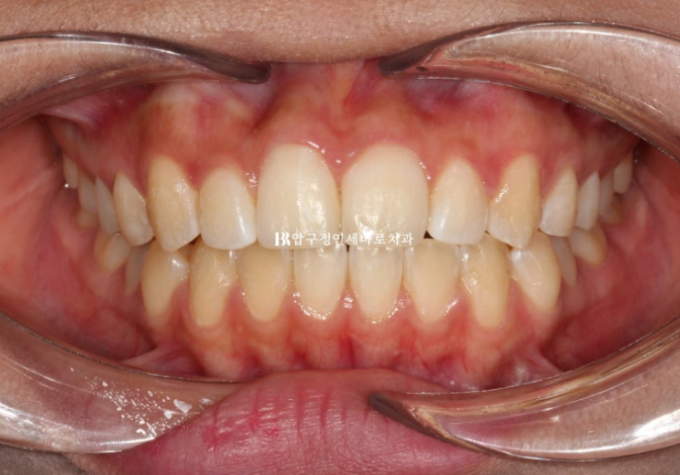

23.12

어금니 교합은 나쁘지 않은 편이라서 단기 앞니 부분교정 권유드렸습니다